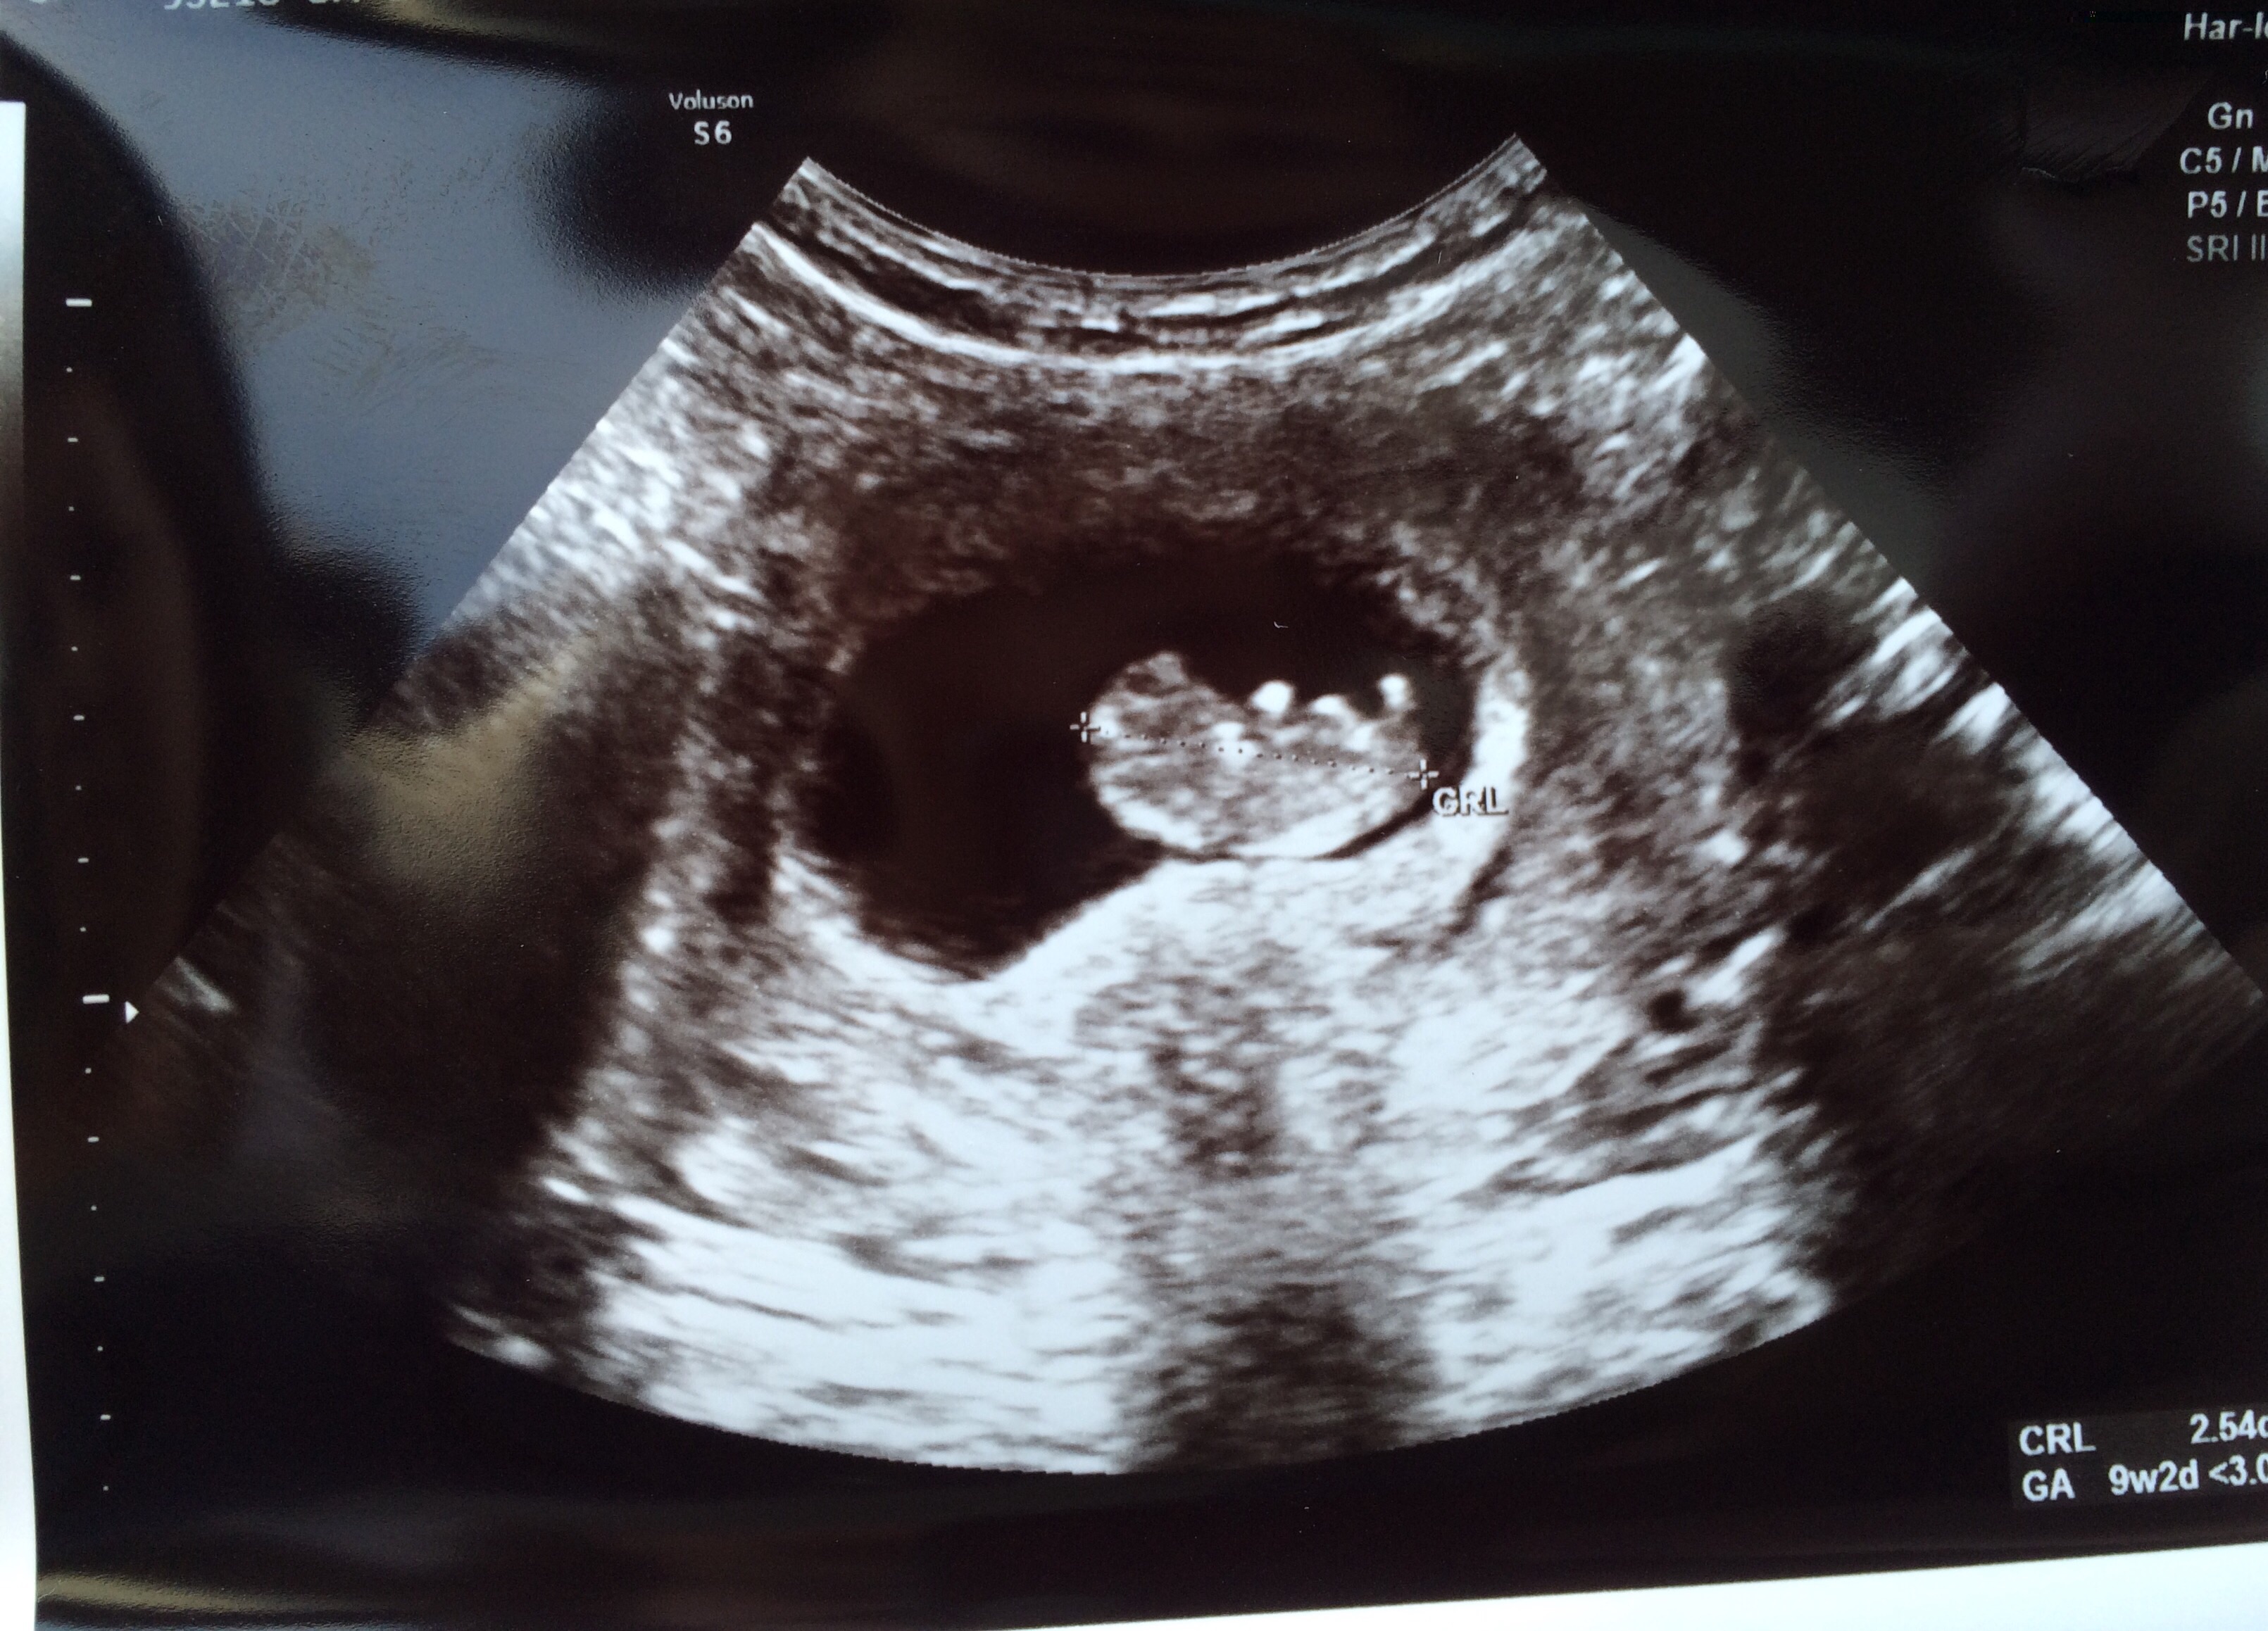

• Our little gummy bear today at 9w2d with a heart rate of 172 :)